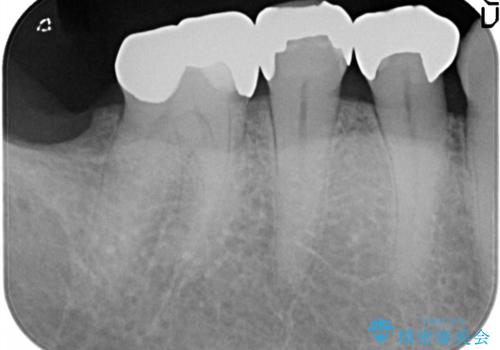

金属の詰め物が外れた。

- 他院で治療した金属の詰め物が外れたことを主訴に来院されました。

PGAインレーにて修復治療を行いました。

ゴールドインレーは適合が良く、割れることもないため、長期的に安定した治療法となります。